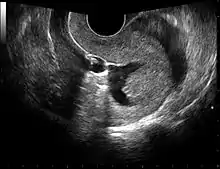

Sonohysterography

Sonohysterography is a specialized procedure by which fluid, usually sterile saline (then called saline infusion sonography or SIS), is instilled into the uterine cavity, and gynecologic sonography performed at the same time. A review in 2015 came to the conclusion that SIS is highly sensitive in the detection of intrauterine abnormalities in subfertile women, comparable to hysteroscopy. SIS is highly sensitive and specific test in the diagnosis of uterine polyps, submucous uterine fibroids, uterine anomalies and intrauterine adhesions (as part of Asherman's syndrome), and can be used as a screening tool for subfertile women prior to IVF treatment.[4]